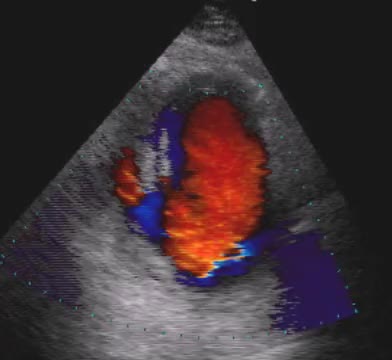

Stenosi mitralica